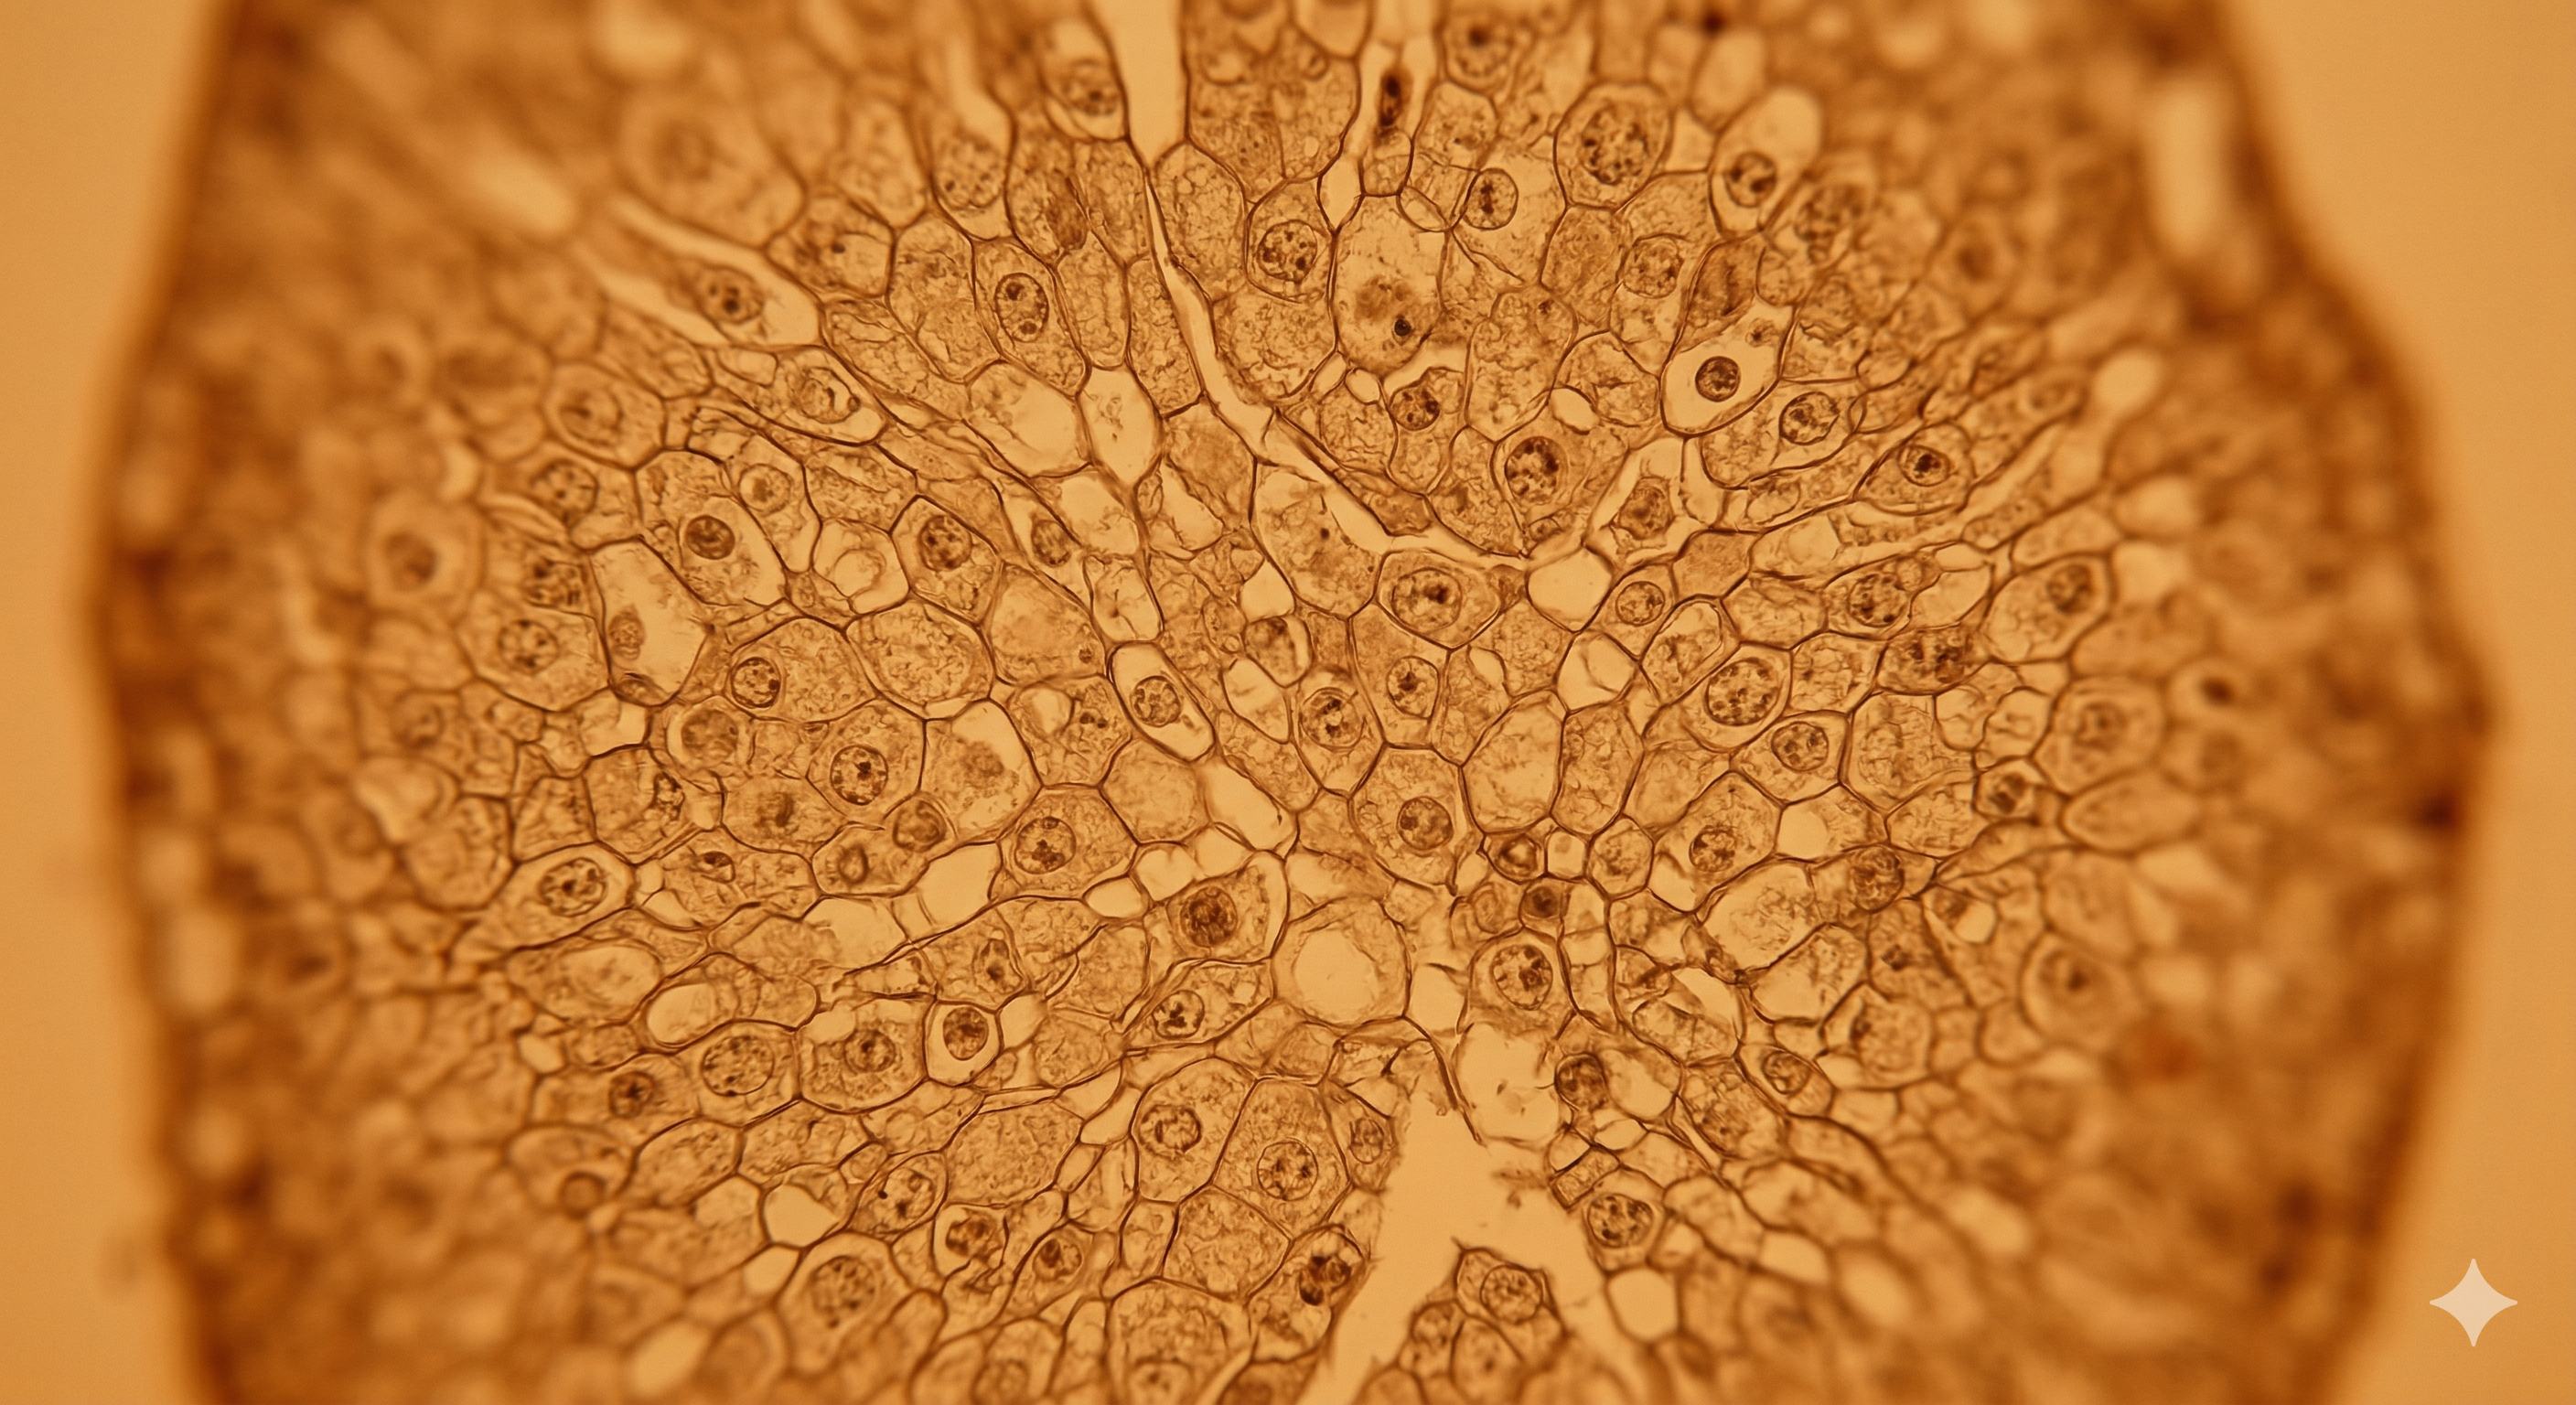

QuPath pipelines, histology segmentation, morphometry automation. Reproducible, annotated workflows — not a one-time script. Already deployed on MOVAT-stained sections for atherosclerosis lesion quantification.

Microscopy tissue cross-section